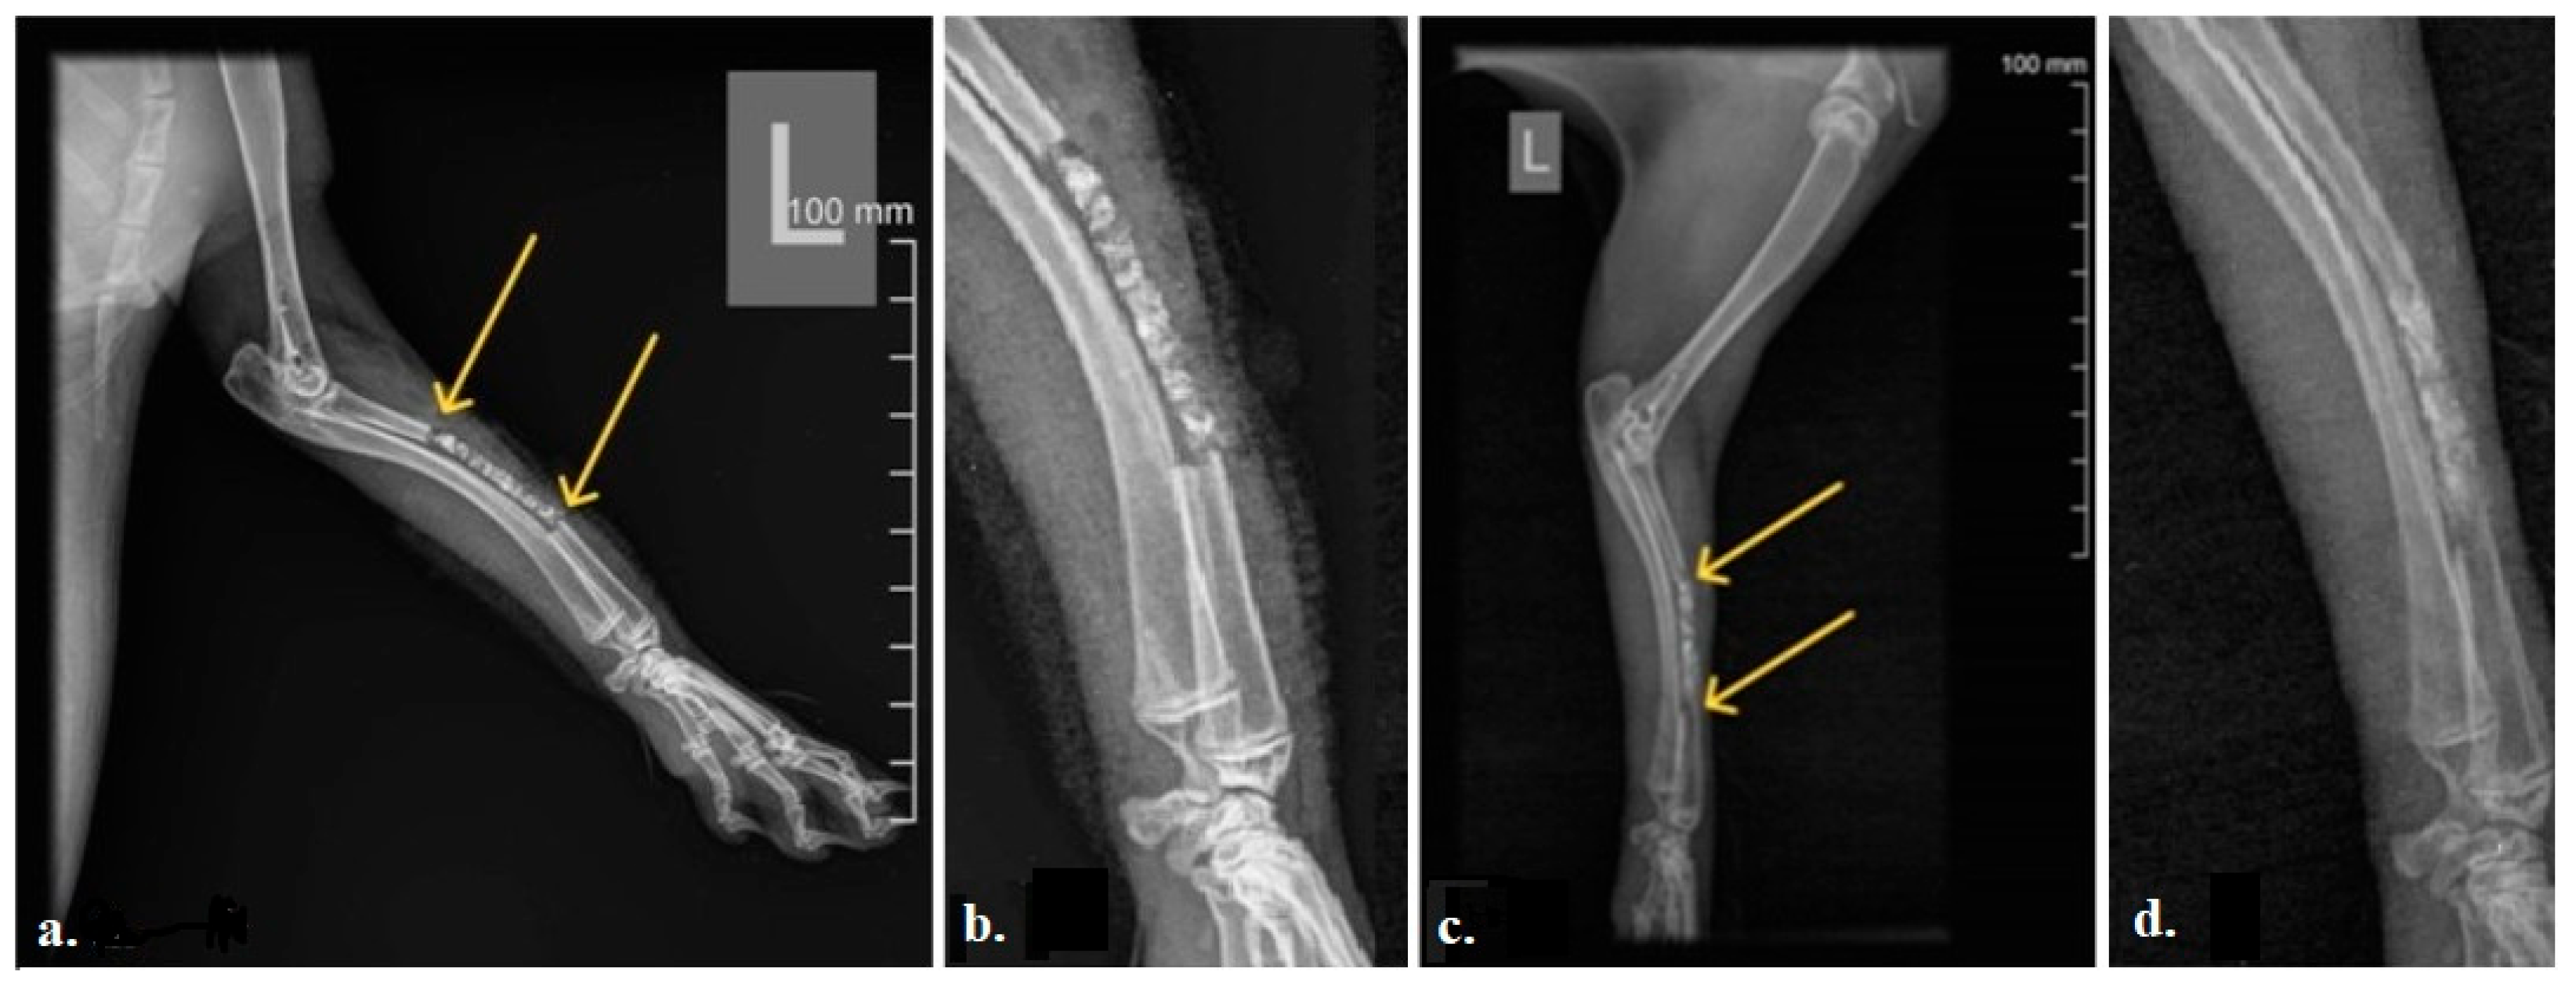

The radiograms of the rabbit radii 12 weeks after implantation showed that the efficiency of bone tissue regeneration in the rabbit radius is lower in the central part of the defect compared to the peripheral areas that were in contact with the old bone (Figure 3). The yellow arrows in Figure 3c point out the complete bone healing at the contact site of the 3D-printed bone graft and old bone, with no radiolucency between the graft and the surrounding bone. Additionally, increased bone density, reflected in a more homogeneous bone structure within the 3D-printed graft compared with the initial radiogram, is noticeable.

Figure 3. Representative radiogram of the rabbit radius: (a) Immediately after implantation of the bone graft. We can see an ideal fitting of the graft into the defect (direct contact of the graft edges with the proximal and distal ends of the previously sectioned bone defect, yellow arrows). (b) Enlarged area of the implant immediately after implantation. (c) 12-weeks post-operative. Complete bone healing at the place of the 3D-printed bone graft near the surrounding bone ends can be noticed (yellow arrows). Also, higher bone density inside the 3D-printed bone graft was noticed. (d) Enlarged area of the implant after 12 weeks.